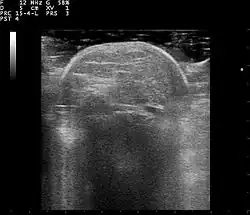

Familial multiple lipomatosis is usually diagnosed through a physical exam via palpation, medical history and imaging studies such as ultrasound, CT scan, or magnetic resonance imaging (MRI). A CT scan is an imaging method that uses x-rays to create images of cross sections of the body, while an MRI uses powerful magnets and radio waves to create images of lipomas and surrounding tissues.[3] Both tests are useful to establish the diagnosis of multiple symmetric lipomatosis, although magnetic resonance imaging provides more details and may be used when lipomas are large, deep, or have infiltrated muscle fibers or nerves. In some cases, a biopsy of the lipomas may be necessary to confirm the diagnosis.[3]